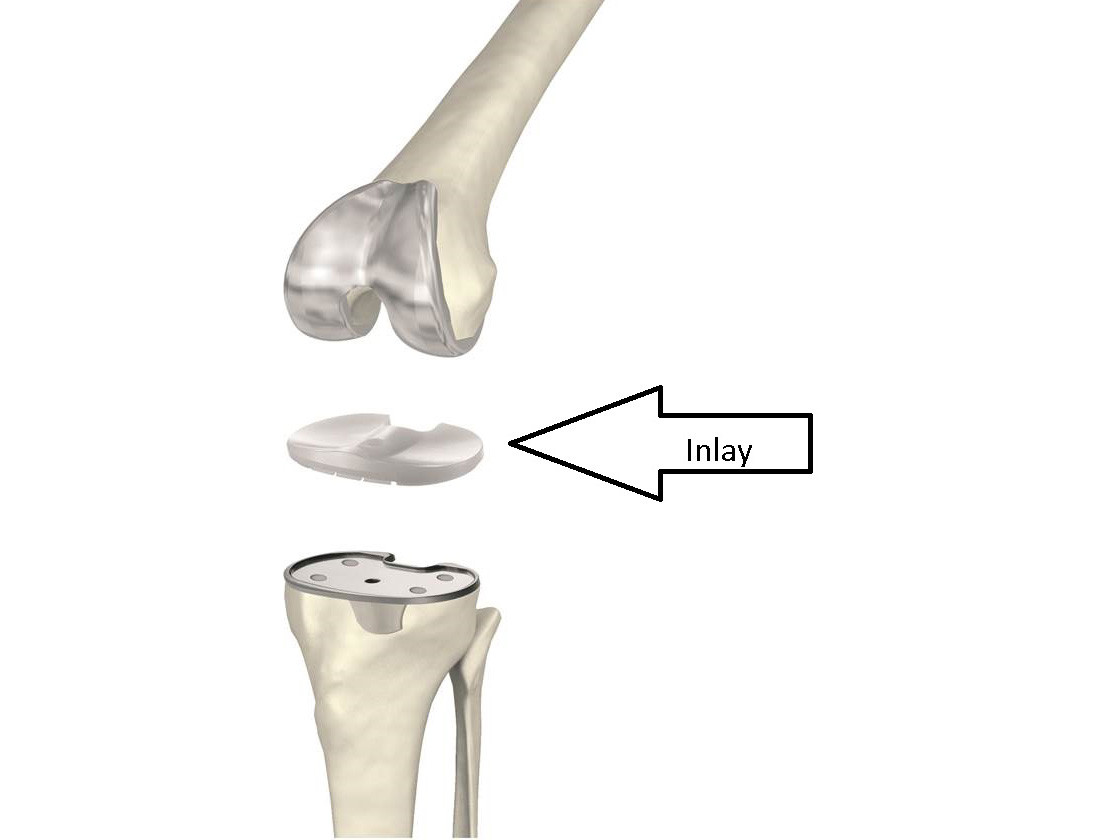

Wechsel des Inlays (Kunststoffeinlage)

Sollte sich im Laufe der Zeit das Inlay abnutzen und eine gewisse Instabilität entstehen, wird der Wechsel des Inlays empfohlen. Vorrausetzung hierfür ist das die übrigen Anteile des Implantates intakt und nicht gelockert sind.